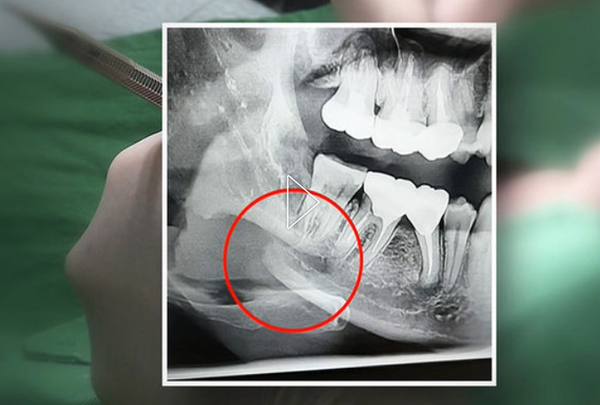

당시 치과에서 사랑니를 발치한 뒤 촬영한 턱 뼈 엑스레이 사진을 보면 오른쪽 아래턱 뼈가 위아래로 두 동강 났다. 사랑니를 뽑던 중 골절된 것이다.